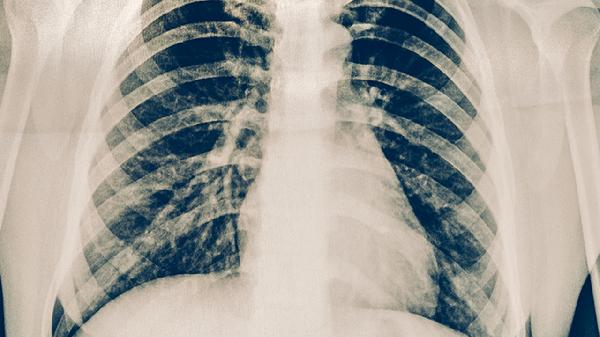

支原体肺炎是由肺炎支原体感染引起的呼吸道疾病,常见症状包括咳嗽、发热、胸痛等。肋骨疼痛可能与剧烈咳嗽导致的肋间肌劳损或胸膜刺激有关。桔红丸主要成分包括化橘红、陈皮、半夏等,适用于痰热咳嗽,其抗炎作用可能间接减轻因咳嗽引发的肋骨不适。但需注意,肋骨疼痛若持续加重或伴随呼吸困难,可能存在胸膜炎等并发症,此时单用桔红丸效果不佳。